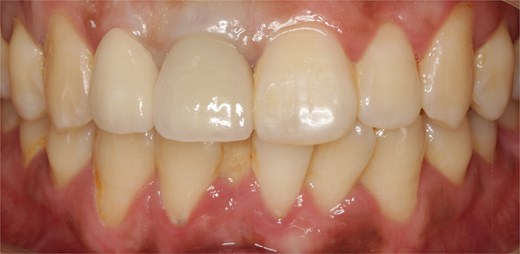

The alveolar crest contour was still stable at 1 year of follow-up, and the patient was satisfied with his final prosthesis, which was in harmony with adjacent teeth (Fig. 6).